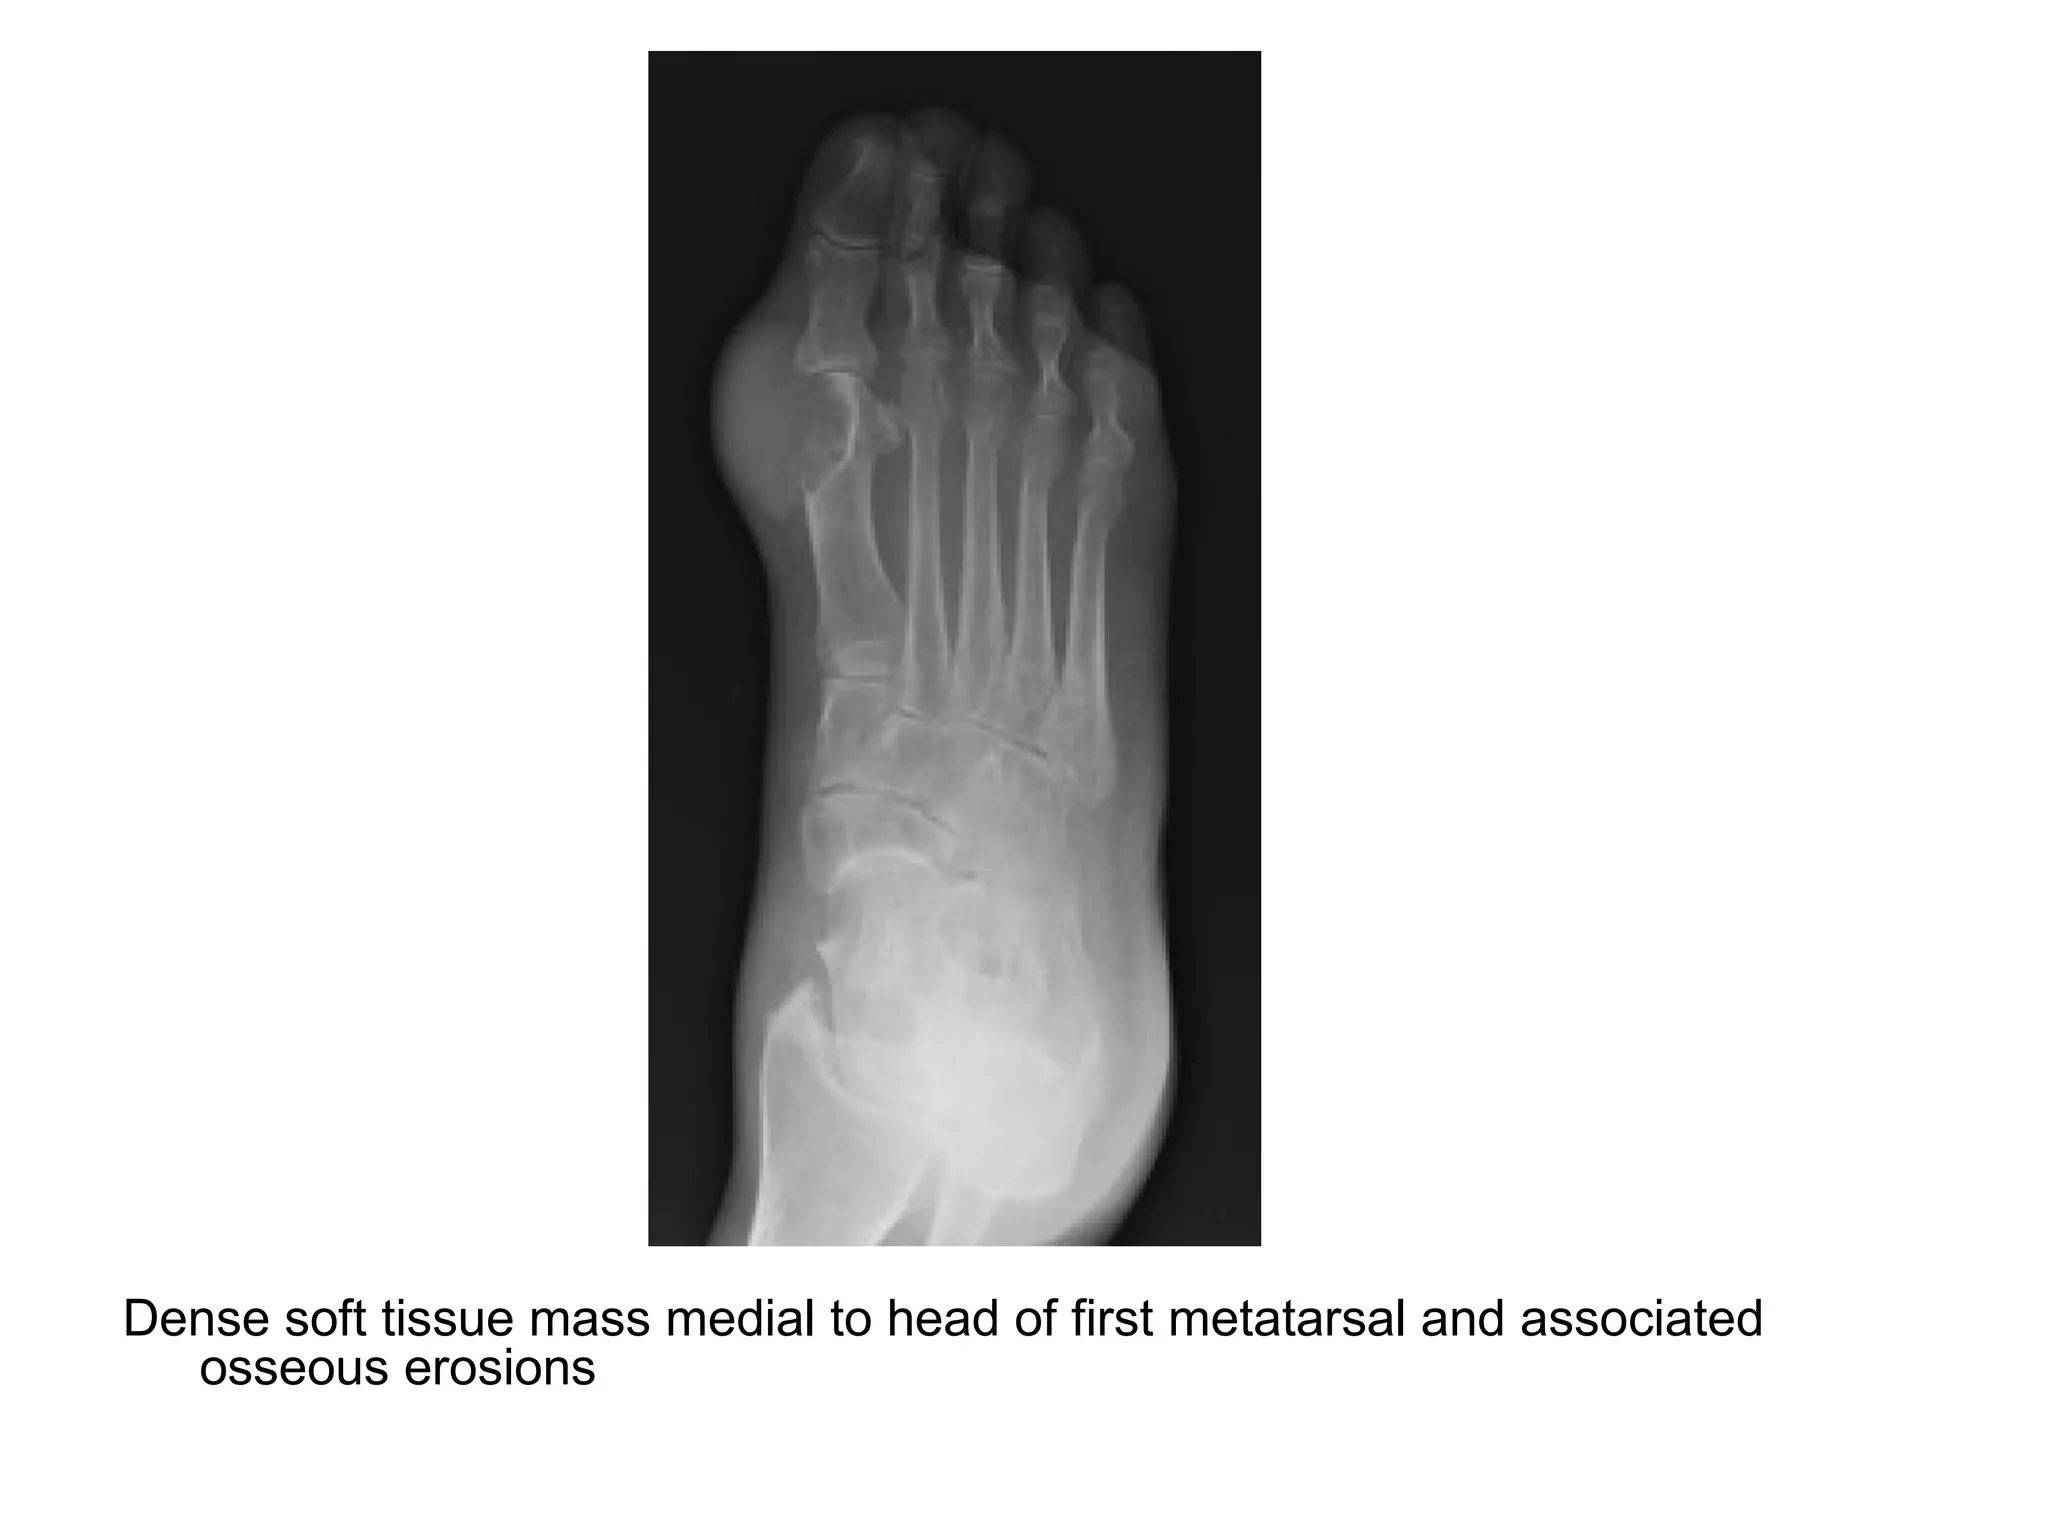

Dense soft tissue mass medial to head of first metatarsal and associated

osseous erosions

The great toe demonstrates extensive juxta-articular erosions

with soft tissue swelling